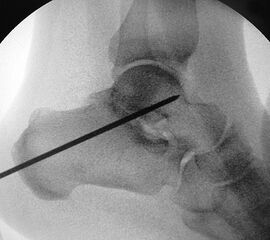

Je nach Operationsziel wird die Arthrodese des Subtalargelenks in verschiedenen Modifikationen durchgeführt. Ist der Rückfuß orthograd ausgerichtet, so erfolgt sie als in situ Fusion, d.h. ohne Korrektur Änderung der Rückfussachse. Liegt eine Rückfuß-Fehlstellung vor, kann diese durch ein additives oder substraktives knöcherndes Vorgehen korrigiert werden 12. Die Fixation der Arthrodese erfolgt üblicherweise mit (kanülierten) Schrauben die über den Tuber calcanei eingebracht werden 3. Eine zweite Schraube zur Sicherung der Rotationsstabilität wird optional über den Processus anterior calcanei im Talushals verankert 4. Der am häufigste verwendete Zugang zum unteren Sprunggelenk verläuft lateral subfibular, alternative Zugänge sind medial oder posterior möglich 56. Ist keine relevante Korrektur notwendig kann der Eingriff auch arthroskopisch durchgeführt werden 78.

Ziel der Korrektur ist eine Reposition des Kalkaneus in eine physiologische 5° valgus Stellung. Eine Überkorrektur in Varus ist in jedem Fall zu vermeiden. Die Stellung wird anschließend mit K-Drähten fixiert, über die kanülierte Schrauben eingebracht werden können."> 155.</li>

Ziel der Korrektur ist eine Reposition des Kalkaneus in eine physiologische 5° valgus Stellung. Eine Überkorrektur in Varus ist in jedem Fall zu vermeiden. Die Stellung wird anschließend mit K-Drähten fixiert, über die kanülierte Schrauben eingebracht werden können." srcset="/assets/images/1/3-9tsh2b2m85xxjf3.jpg 1x, /assets/images/q/3-q5j2bj6y0h8725z.jpg 1.5x, /assets/images/k/3-h9kd23kj30b48p9.jpg 2x" width="270" height="240" loading="lazy">

Schraubenfehllage: Bei der intra-operative Röntgen-Kontrolle muss der Fuß exakt seitlich und das obere Sprunggelenk ap eingestellt werden, um die korrekte Lage der Schrauben beurteilen zu können.